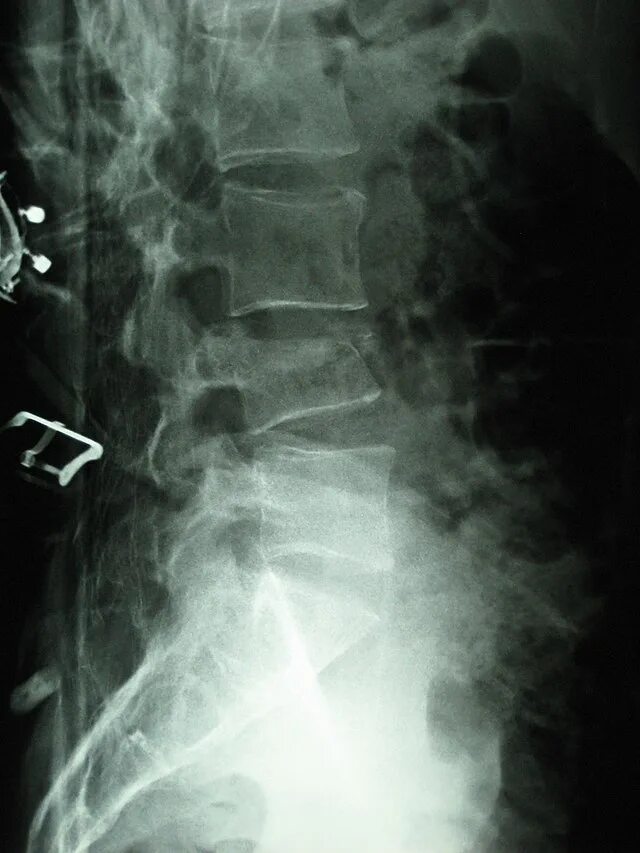

Компрессионный 4 позвонка